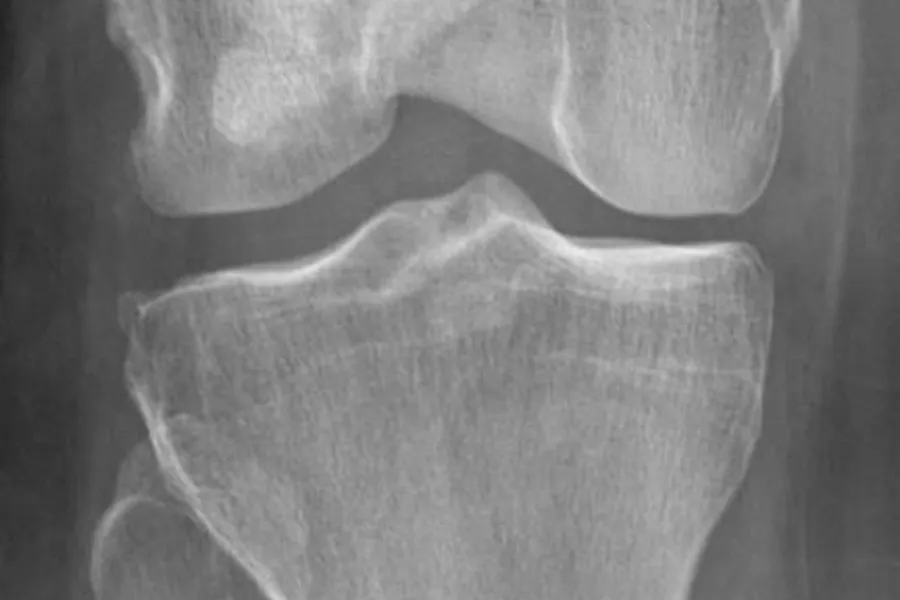

- Lite artrose på røntgen (KL grad <3)*

*Kellgren-Lawrence grad 3:moderate multiple osteofytter, avsmalning av ledd, noe sklerosering og mulig deformasjon av benender